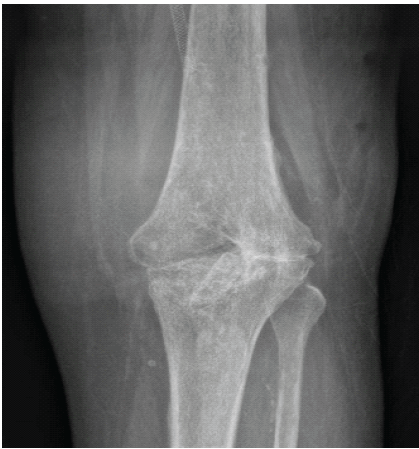

Several months later, he developed pain and swelling of the orthopedic knee prosthesis (Fig. 4).

Figure 4. Infected right total knee arthroplasty with implant loosening. Anteroposterior and lateral radiographs demonstrating loosening of the right knee prosthesis consistent with prosthetic joint infection.